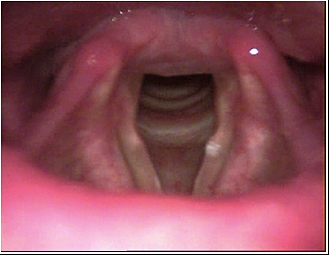

JFC Atrofia senil de laringe

JFC Disfunción laríngea senil.